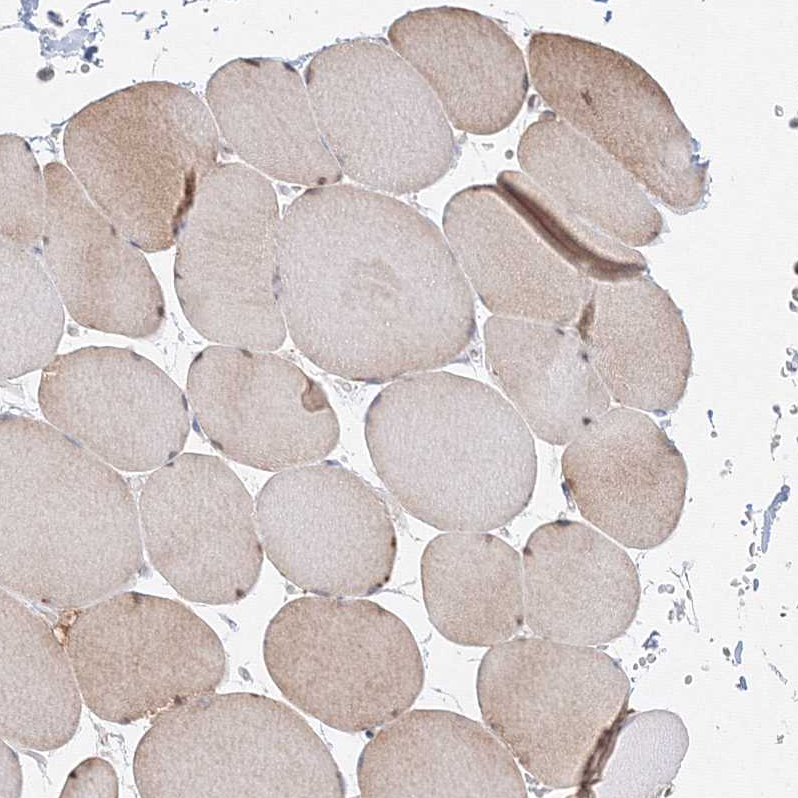

Immunohistochemical staining of human small intestine shows strong nuclear positivity in glandular cells.